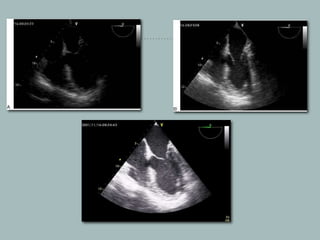

Figure 8: In this mid-esophageal four-chamber view, the TGC toggles at the level of the ventricles have been manipulated to illustrate the high gain at that

particular depth (arrow)

igure 9: Transgastric mid-papillary short axis

view. In panel A the septal and lateral wall

areas are poorly defined. In panel B both

wall regions are adequately imaged by

increasing the lateral gain. PPM-

Posteromedial papillary muscle and APM -

Anterolateral papillary muscle

Lateral gain compensation (LGC)

LGC is similar to TGC except they alter image gain at specific

angle sectors in a direction perpendicular to TGC. It is useful to

image hypoechoic images caused by suboptimal positioning.